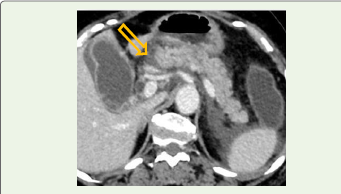

Figure 1: Contrast-enhanced CT showing preserved pancreatic

enhancement with mild peripancreatic fat stranding (arrow), consistent with

mild acute pancreatitis.